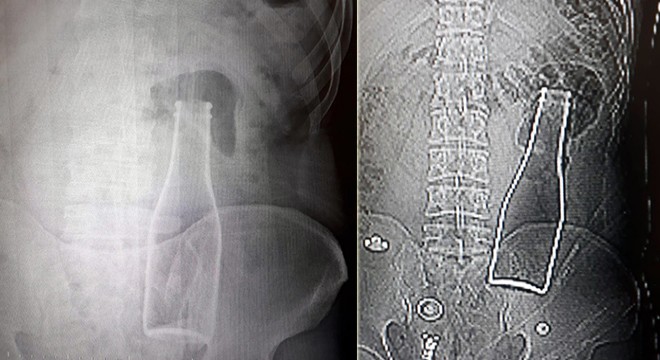

Vücudundan şişe çıkan Afgan genç: Yanlışlıkla oldu

KARAMAN'da karın ağrısı şikayetiyle gittiği hastanede çekilen röntgen ...